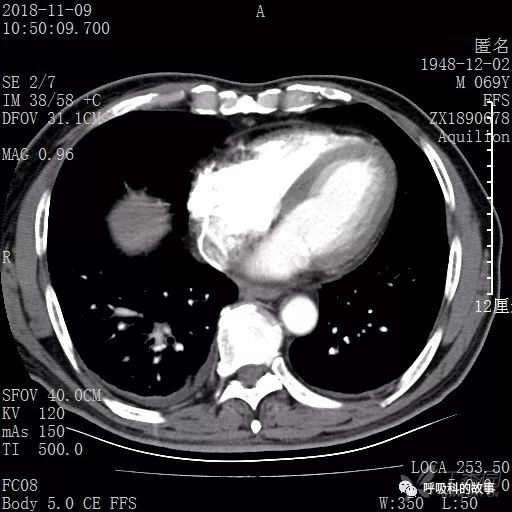

胸部增强CT示右肺门占位伴远端阻塞性肺炎,纵膈、右肺门、右侧颈根部、右侧腋下及肝门部肿大淋巴结。两侧胸腔少量积液。

纵隔窗的增强CT